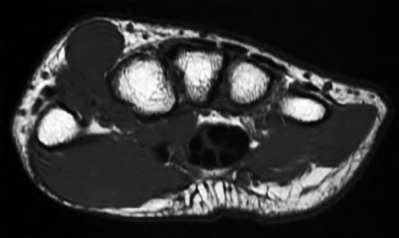

A 50-year-old woman is diagnosed with carpal tunnel syndrome. She is prescribed a cock-up wrist splint at 30 degrees of extension to wear at night. This splint has what effect on the carpal tunnel?